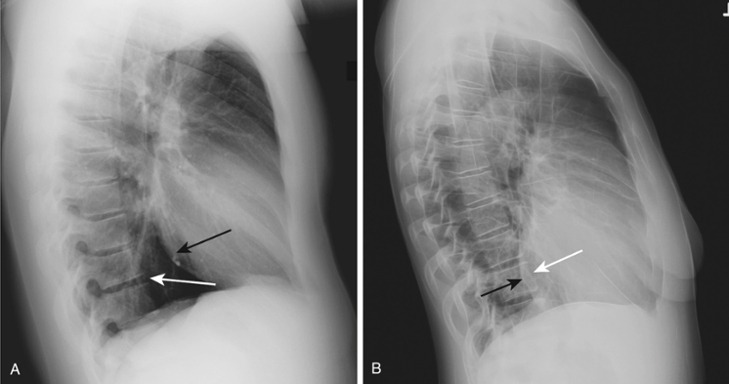

Frontal and lateral views of the chest demonstrate airspace disease on the lateral film (B) in the right lower lobe (white arrow) that may not be immediately apparent on the frontal film (you can see the pneumonia in the right lower lobe in [A] [black arrow]).

In this case, a right lower lobe pneumonia superimposed on the lower spine on the lateral view makes the spine appear “whiter” (more dense) just above the diaphragm. This is called the spine sign.